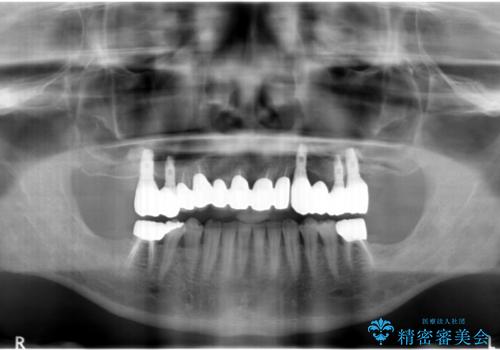

- 他院で上顎は全て抜歯し、入れ歯にする必要があると言われ相談に来院されました。

検査の結果、重度の歯周病であることから保存が難しい歯は抜歯を行いインプラントを、残すことが可能な歯には再生治療を含めた歯周病治療を行いより多くの歯を残す歯周病治療を計画します。

上顎は、残っている前歯も揺れがあり残すためにはクラウンでつなぐ歯周補綴が必要な状態です。

また咬合負担に不安のある前歯を助けるためにも、臼歯部にインプラント補綴を行いしっかりとかめる状態とすることも大切です。